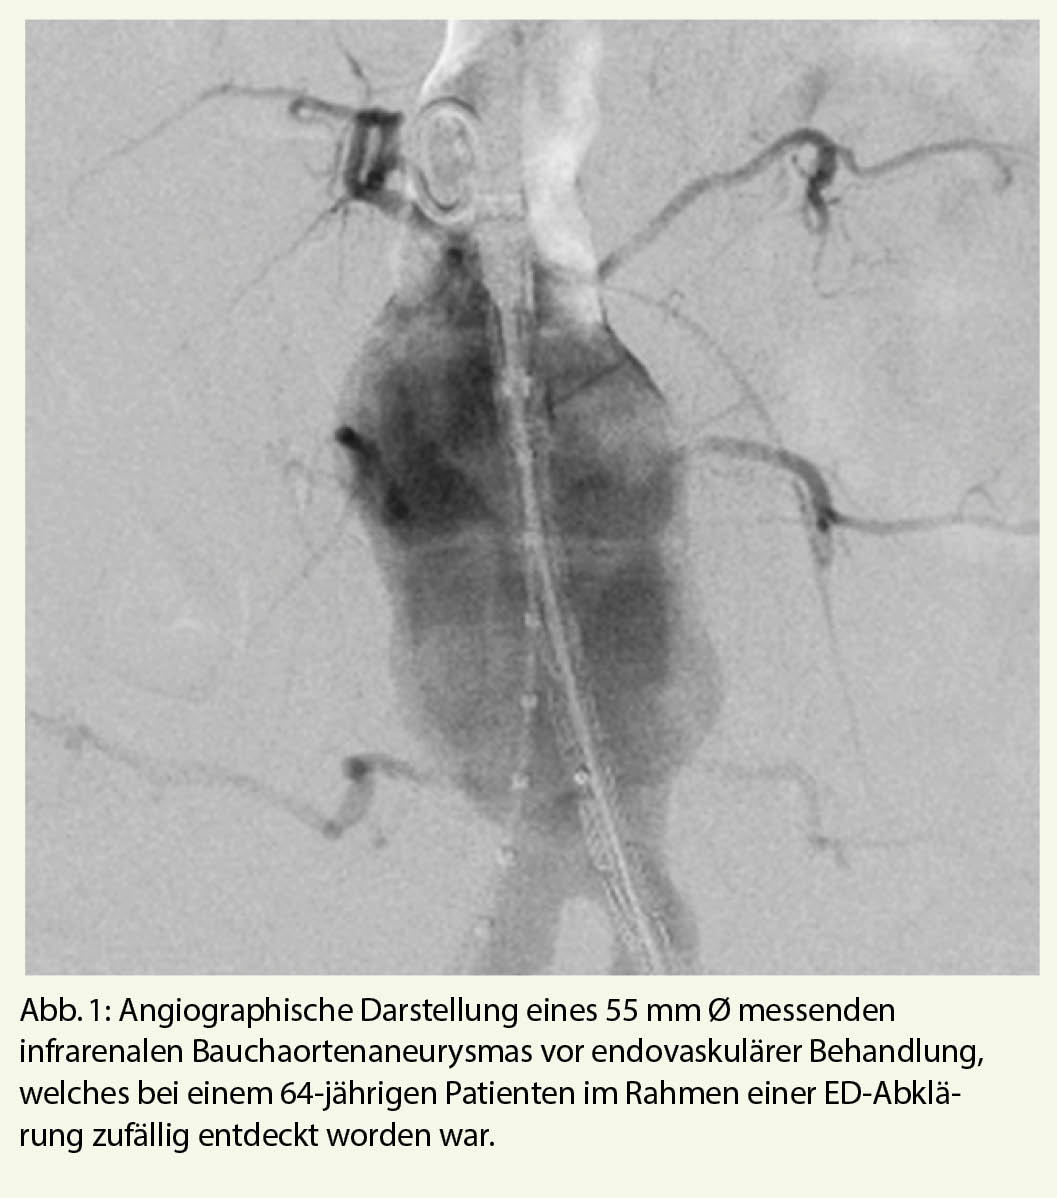

Sobald die Diagnose einer arteriell bedingten ED gesichert ist, empfiehlt sich ein fachärztliches Workup. Häufig finden sich bei Patienten mit arteriell bedingter ED auch Pathologien in anderen arteriellen Stromgebieten (Abb. 1, 2).

Die ZEN Studie beschäftigte sich mit der klinischen Effizienz der Implantation Medikamenten-beschichteter Koronarstents in Pudenda Obstruktionen (11). Die Obstruktionen waren fokaler Natur (durchschnittliche Läsionslänge 18 mm), der durchschnittliche Gefässdurchmesser betrug 2,6 mm. In allen Fällen wurde ein technischer Angioplastie- bzw. Stent-Erfolg verzeichnet, wobei sich im Nachgang herausstellte, dass bei 5 von 30 Patienten aus Versehen nicht erektions-bezogene-Arterien gestentet wurden, was die anatomische Komplexität dieser Eingriffe unterstreicht. Im Rahmen neuerer Untersuchungen zeigte eine Arbeitsgruppe, dass selbst die technisch nicht triviale Angioplastie in Händen erfahrener Interventionalisten sicher ist (14).

Eine detaillierte Studie von uns zeigte, dass die endovaskuläre Behandlung mit atherosklerotischer ED sicher und wirksam war. Der Erfolg wurde bei 49 (98%) von 50 Patienten erzielt. Nach 12 Monaten erreichten 65% der Patienten eine Verbesserung nach IIEF-6-Scores und die Veränderung des Scores war konsistent (15). So lange es noch keine randomisierten Studien gibt, sollte die Stentbehandlung für ED Patienten reserviert sein, die nicht auf konservative Therapiemassnahmen (PDE-5-Hemmer oder intrakavernöses Prostaglandin) ansprechen. Abbildung 4 zeigt eine komplexe Intervention bei einem 66-jährigen ED-Patienten mit Stenose der Penisarterien-Bifurkation. In koronarer Bifurkations-Technik wird der Abgang der A. cavernosa zunächst mit einem Sirolimus-beschichteten Stent überstentet (Abb. 4b) um den Fluss in die für die Rigidität der Eichel wichtige A. dorsalis penis zu gewährleisten. Im Anschluss wird die für die Rigidität des proximalen Penisschaftes wichtige A. cavernosa mit einem Draht sondiert und mit einem weiteren beschichteten Stent durch die Maschen hindurch gestentet (Abb. 4c).